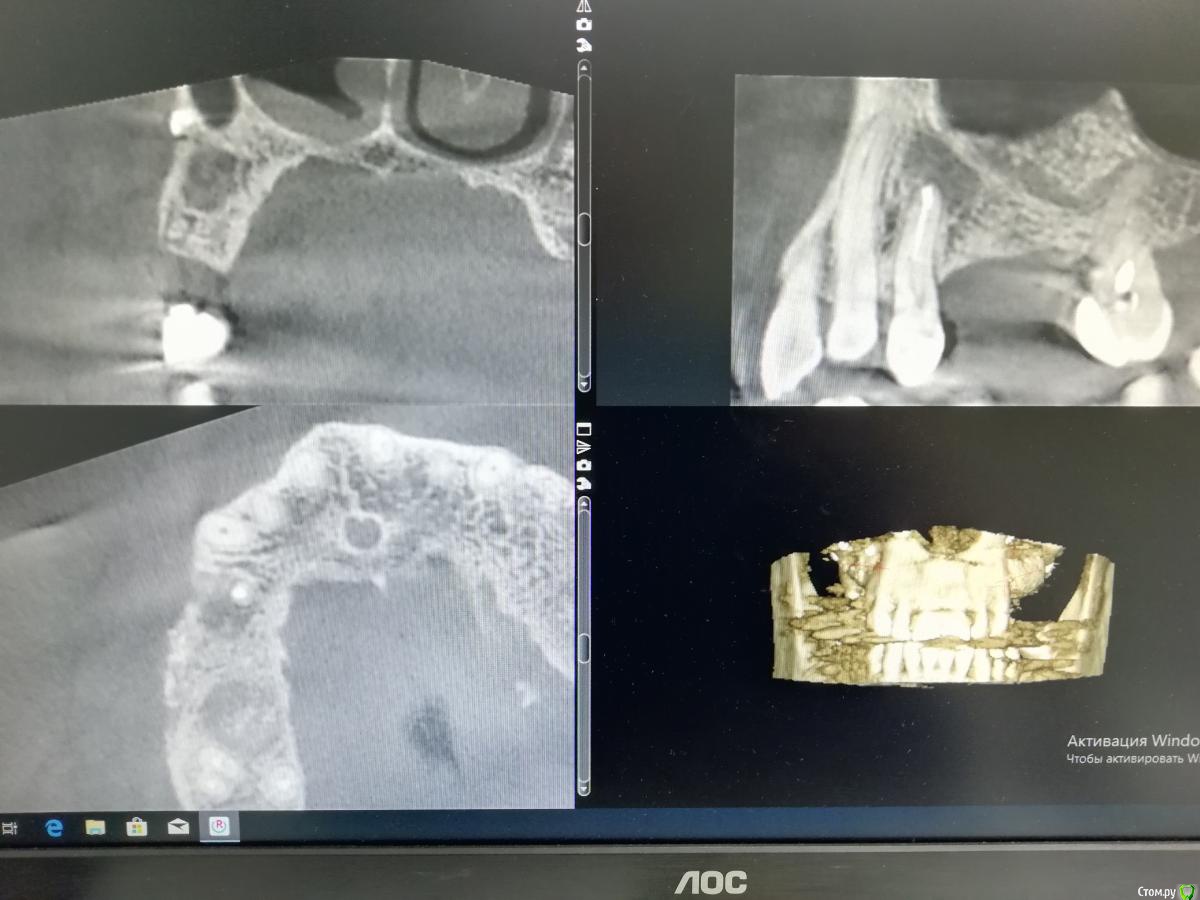

___49___ Опубликовано 23 декабря, 2019 Поделиться Опубликовано 23 декабря, 2019 (изменено) 6 месяцев назад , проведено РВК двух корней 14 зуба с ретроградкой триоксидентом, в дефект заложена гемостатическая губка на линкомицине, в месте доступа подсыпан чистый ксено с излишком . Синуслифтинг в области 16 и 15 го отсутствующих зубов , Ксено +ауто и под них 3 губки на линкомицине (участок с молодыми костными балками без ксено на фото - между графтом и старой границей кости ) . Область окна при синусе и немного вестибулярнее смесь ксено + ауто с излишком ( как говорил учитель если есть ширина то будет и высота , в том числе и как опора для мягкотканной пластики если понадобится ) . все перекрыто резорбируемой мембранной на пинах. Азитромицин перед операцией . Изменено 23 декабря, 2019 пользователем ___49___ 1 Ссылка на комментарий

___49___ Опубликовано 23 декабря, 2019 Автор Поделиться Опубликовано 23 декабря, 2019 НКР вестибулярно в области 24 зуба ксено +ауто, НКР вертикально в области 26го зуба ксено +ауто(утрамбовано очень плотно) , Синуслифт в области 26 и 25 го ксено +ауто, из чистого ксено сделана боковая поддержка вестибулярно для будущих мягких тканей в области 26 и 25 , все перекрыто резорбируемой мембраной на пинах.. Через 4.5 месяца удален 27 ой зуб , заложена губка плотно ( уже появляются первые балочки на Rg). 1 Ссылка на комментарий

___49___ Опубликовано 23 декабря, 2019 Автор Поделиться Опубликовано 23 декабря, 2019 Планирую Импланты:обл16 - 6х8 обл 24- 4.5х12обл 26- 6х12 Коментарии, критика , свое виденье планирования уважаемые коллеги высказывайте. Спасибо . Ссылка на комментарий

___49___ Опубликовано 28 декабря, 2019 Автор Поделиться Опубликовано 28 декабря, 2019 из чистого ксено!? Да это чистый ксено. Будет боковой поддержкой для мягких тканей, больше шансов получить более "высокую" десну . Я про это) На сгустке само хорошо заживает. согласен с Вами , часто оставляю просто на сгустке , но при одновременном РВК с инфицированным участком и лифте с НКР в этой же области я просто перебдел , обидно было бы получить закисшее из-за обсеменения из зоны РВК . можно подробнее, как для студента ) Дмитрий Владимирович не прибедняйтесь . Ссылка на комментарий